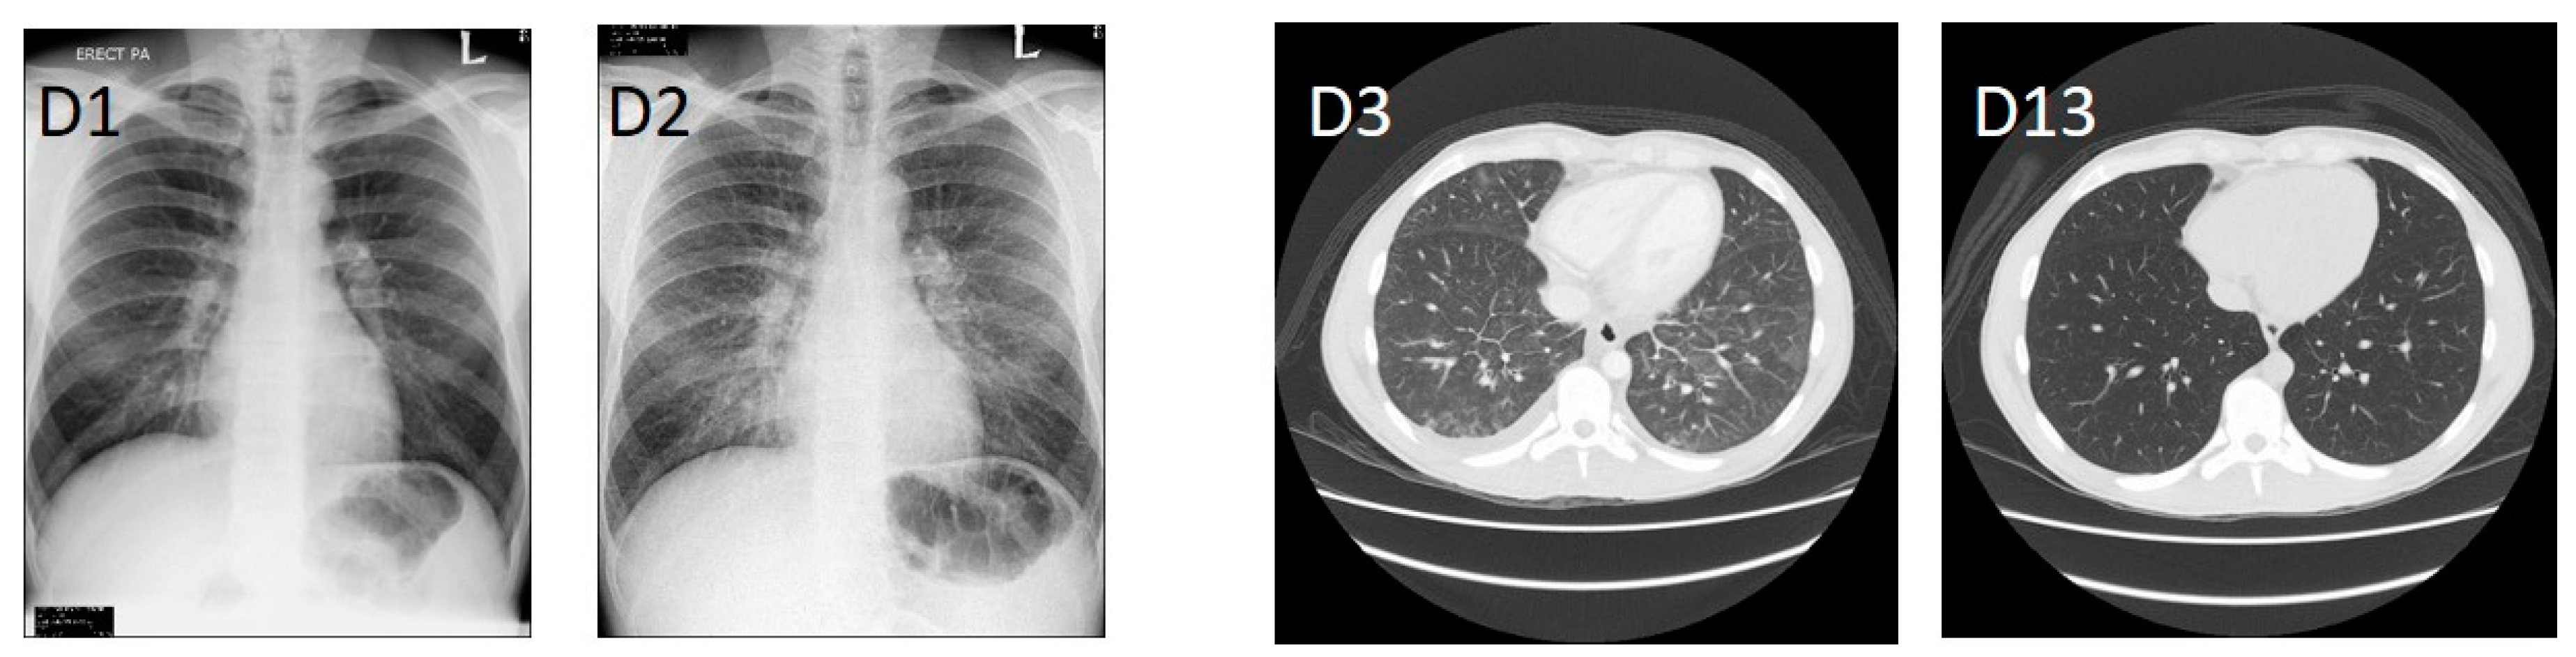

Figure 1.

Chest X-rays upon admission (D1) and subsequent day (D2). Contrast-enhanced CT scan after oral and intravenous contrast administration at the day of hypotensive shock (D3), and post-treatment (D13).

A previously-healthy 23-year-old British male presented to Jesselton Medical Centre (JMC), Kota Kinabalu, Sabah, Malaysia, with an acute febrile illness. The patient had been in Sabah for a period of three months prior to becoming ill. Earlier on the day of admittance at JMC the patient had attended a clinic from where he was discharged to wait two days for the results of diagnostic tests (dengue and malaria), evidently not recognising the severity of his symptoms. Upon admission to JMC (day 1, D1), the patient reported onset of symptoms four days prior, having high fever (over 39 °C), headache, dry cough, sweating, diarrhoea, joint and muscular pain, appetite loss, nausea, confusion and light-headedness. Physical examination indicated a mild rash of small, undefined, scattered red dots on the limbs and abdomen and mild haemoptysis, at which point he was admitted to the intensive care unit (ICU). Haematology and biochemistry results indicated severe thrombocytopenia, leukopenia, lymphopenia, and a mild cholestasis (Table 1). He was haemodynamically stable, his lungs were clear, and there was no evident hepatosplenomegaly. Following admission, the patient’s condition rapidly deteriorated. The admission chest X-ray was normal, but a repeat X-ray the following day showed clear pleural effusion (Figure 1). On D3 post-admission, the patient went into hypotensive shock (BP 70-80/30-40). CT scans showed pleural effusion in the right lung as well as ground-glass opacities in the dependent portion of the lungs, bilaterally (Figure 1). Additionally, the liver and the spleen were enlarged at 21 and 15 cm, respectively. Signs of abnormal liver function became evident on D5 post-admission and were persistent for more than two weeks (Table 1). Antibiotic therapy commenced with ceftriaxone 2 g o.d. and doxycycline 100 mg b.d., with the former discontinued after the hypotensive shock on D3 post-admission, and the latter on D7 post-admission. Due to the patient’s inability to take oral medication, the lack of diagnosis, and to ensure a broad coverage of illnesses, meropenem 1 g tds and azithromycin IV 500 mg o.d. were started on D3 and D4 post-admission for four and seven days respectively; intravenous doxycycline, the preferred choice for this case, is not available in Malaysia. The patient became afebrile on D5 post-admission and subsequently improved over the following 2 weeks. He was discharged after 23 days hospitalization when he was fit to travel to his home country, where he made a full recovery.